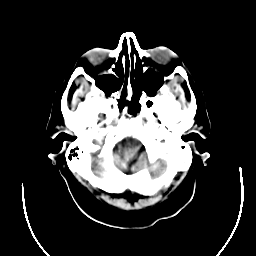

CT Study #3 -- Slice #4